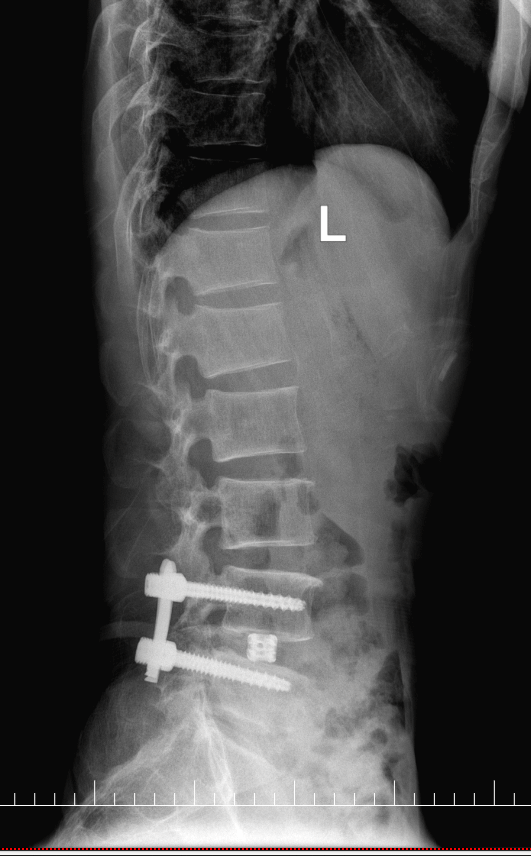

手术首先采用经皮椎弓根螺钉固定技术,通过几个微小切口植入椎弓根螺钉,为脊柱提供稳定支撑。医生在高清影像设备引导下精准操作,每个步骤都准确无误。

最后,植入3D打印椎间融合器完成融合。这种融合器根据患者解剖结构个性化定制,表面特殊纹理能更好地与骨组织结合,大大提高了融合成功率。

术后复查

术后,在医护人员的精心护理和康复指导下,黄先生的恢复情况超出了预期。术后第一天,他就能在床上进行简单的肢体活动,腰部及下肢的疼痛麻木感明显减轻。术后第三天即可下床行走,照片中的他,已经能自主行走,虽然步伐还不算太快,但相比术前的艰难行走,已经有了天壤之别。